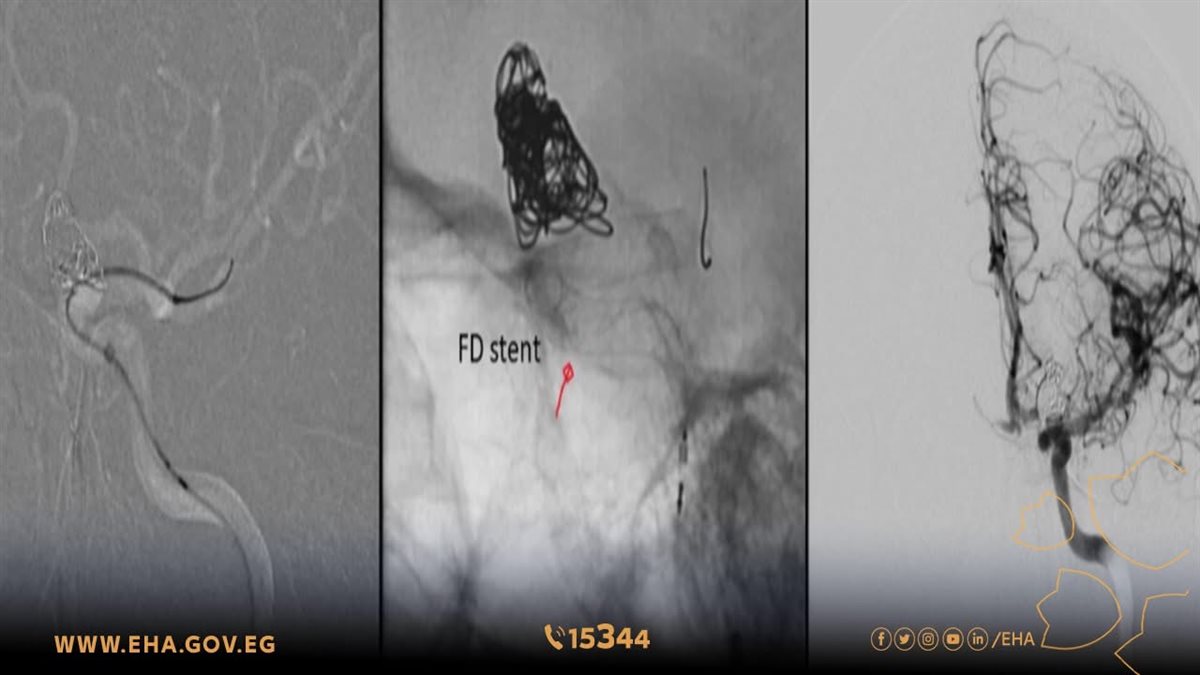

وتمكن الفريق الطبي بمهارة فائقة من إجراء 6 حالات قسطرة علاجية معقدة، تضمنت حالتين لتركيب "دعامات مغيرة لمسار الدم" مدعومة بالملفات الحلزونية، وهي تقنية طبية متقدمة وعالية المهارة تستخدم لعلاج حالات التمدد الشرياني الدقيق بالمخ وتجنيب المرضى مخاطر النزيف المفاجئ.